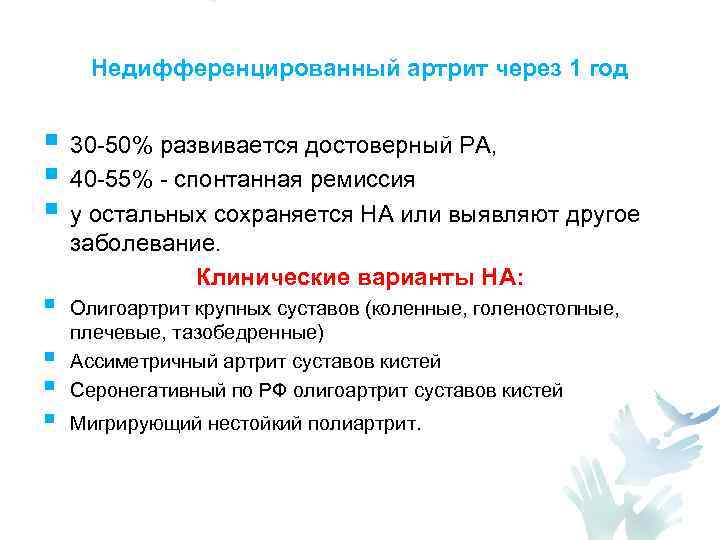

Недифференцированный артрит через 1 год § 30 -50% развивается достоверный РА, § 40 -55% - спонтанная ремиссия § у остальных сохраняется НА или выявляют другое § § заболевание. Клинические варианты НА: Олигоартрит крупных суставов (коленные, голеностопные, плечевые, тазобедренные) Ассиметричный артрит суставов кистей Серонегативный по РФ олигоартрит суставов кистей Мигрирующий нестойкий полиартрит.

Недифференцированный артрит через 1 год § 30 -50% развивается достоверный РА, § 40 -55% - спонтанная ремиссия § у остальных сохраняется НА или выявляют другое § § заболевание. Клинические варианты НА: Олигоартрит крупных суставов (коленные, голеностопные, плечевые, тазобедренные) Ассиметричный артрит суставов кистей Серонегативный по РФ олигоартрит суставов кистей Мигрирующий нестойкий полиартрит.